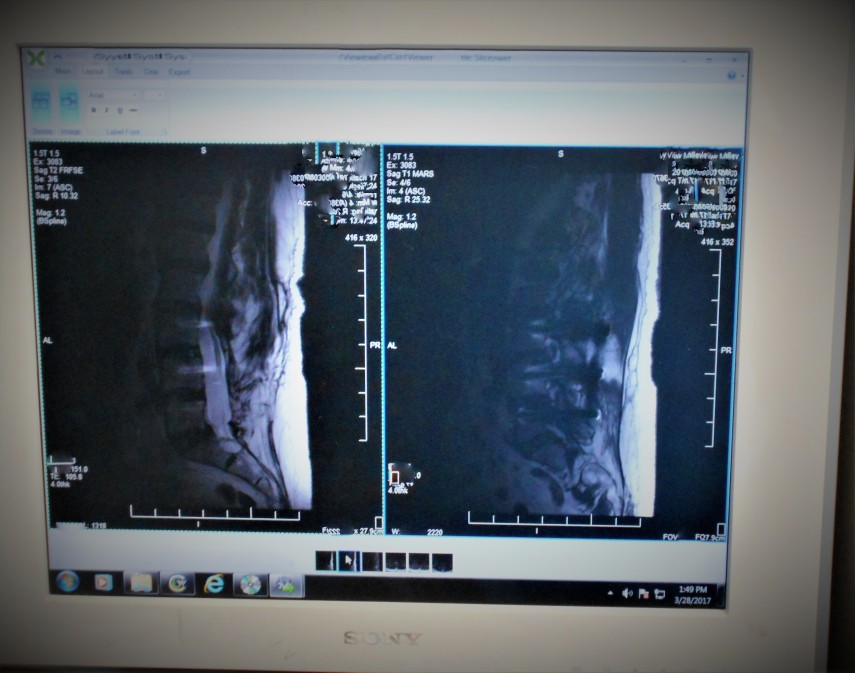

Avec le temps et en fonction de votre métier, les disques lombaires protégeant les vertèbres s’usent et finissent par devenir très fins, entrainant des douleurs atroces dans la région lombaire. Après la prise d’antalgique, il est conseillé aux patients de se rendre auprès d’un neurochirurgien pour évaluer avec un scanner une possible intervention chirurgicale. Vous êtes en recherche d’un spécialiste Neurochirurgien à Bordeaux, nous vous conseillons de cliquer sur ce lien pour prendre rendez-vous.

Principale cause de sciatique et d’immobilisation complète du dos, les hernies discales nécessitent une prise en charge rapide. L’usure du disque entraine souvent une excroissance de celui-ci venant appuyer de façon naturelle sur les racines nerveuses de la moelle épinière, entrainant douleur et impossibilité de bouger.